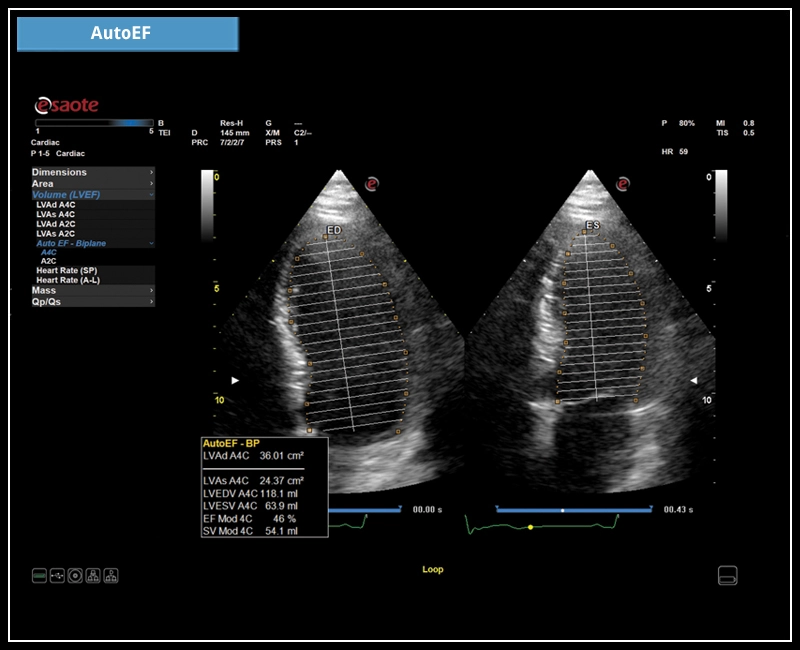

Das neue MyLab™X6 von Esaote macht Ihren Workflow so effizient und reibungslos, dass es nicht nur die Produktivität erhöht, sondern auch Ihre klinischen Leistungen verbessert. Es deckt alle klinischen Anforderungen von abdominalen bis zu endokrinologischen Anwendungen ab, um eine sichere Diagnose zu stellen und die bestmögliche Therapie und Nachsorge zu bieten.